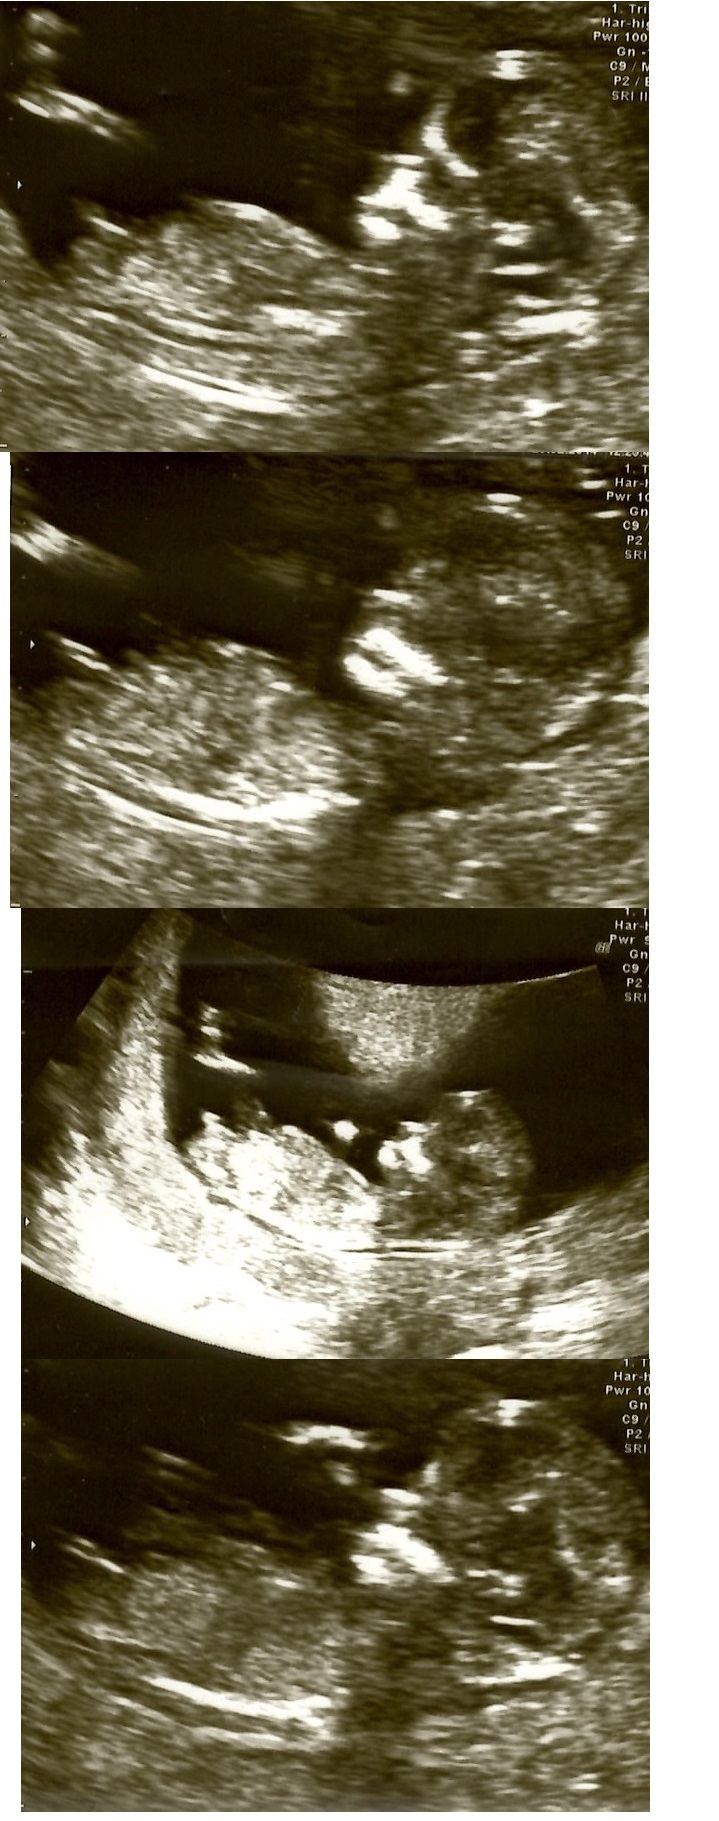

Hi everybody - I have been looking through numerous online ultrasound images at 12 weeks and I just can't work it out

Any predictions please?

Boy- the 3rd pic especially shows classic boy nub- congrats!!!

I too will say boy from the third picture.

We had our 20-22 week scan last week and it was revealed to be a baby boy